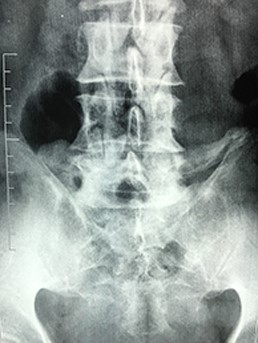

A 42-year-old female presented to the clinic with a history of chronic low back pain. She reported no relevant medical history. She had already been treated in the last 4 years by general practitioners with analgesics and home based physiotherapy with no satisfactory results. She had two previous admissions to the emergency department where morphine was prescribed to control the pain on her lower back. She was under ambulatory treatment with diclofenac, and tizanidine with partial relief of symptoms. Her main complaint was pain on the lower lumbar back with no radiation to the lower extremities. In her physical evaluation she presented limitation to full rotation and bending of the lumbar spine due to pain. Lasegue sign was negative, sensitivity, reflexes, sagittal balance, distal muscular strength and pulses were normal. Radiographs showed an overdeveloped left transverse process of the fifth lumbar vertebra which contacts with the sacrum at the left sacral wing with signs of degeneration at the same site (Fig. 1). Magnetic resonance imaging (MRI) studies were obtained (Figs 2–5). The patient was taken to the operating room where infiltration with 1 mL of lidocaine and 40 mg of Triamcinolone was performed in the pseudoarticulation between the left transverse process and the sacrum under fluoroscopic guidance. She reported a complete relief of pain after the procedure. At three months follow-up she was managed with strengthening and stabilizing exercises for the lumbar spine and postural education was initiated. She remains asymptomatic at her 12 months follow up.

Radiographs showing an overdeveloped left transverse process, which contacts with the sacrum left sacral wing (Castelvi’s Type IIa).

Plain radiographs of the lumbosacral spine demonstrate 76–84% effectiveness to detect LSTV. Ferguson radiographs of the lumbosacral spine (AP radiograph with a 30° cranial angulation) presents with a higher sensitivity in detecting LSTV. Mid-sagittal T2-weighted MRI presents with 80% sensitivity and specificity for the diagnosis, with bone marrow edema as one of the most common findings [5]. CT scan is a complimentary imaging resource that helps defining bone structures, osteophytes and the state of the pseudoarticulation of the fifth transverse process [6].